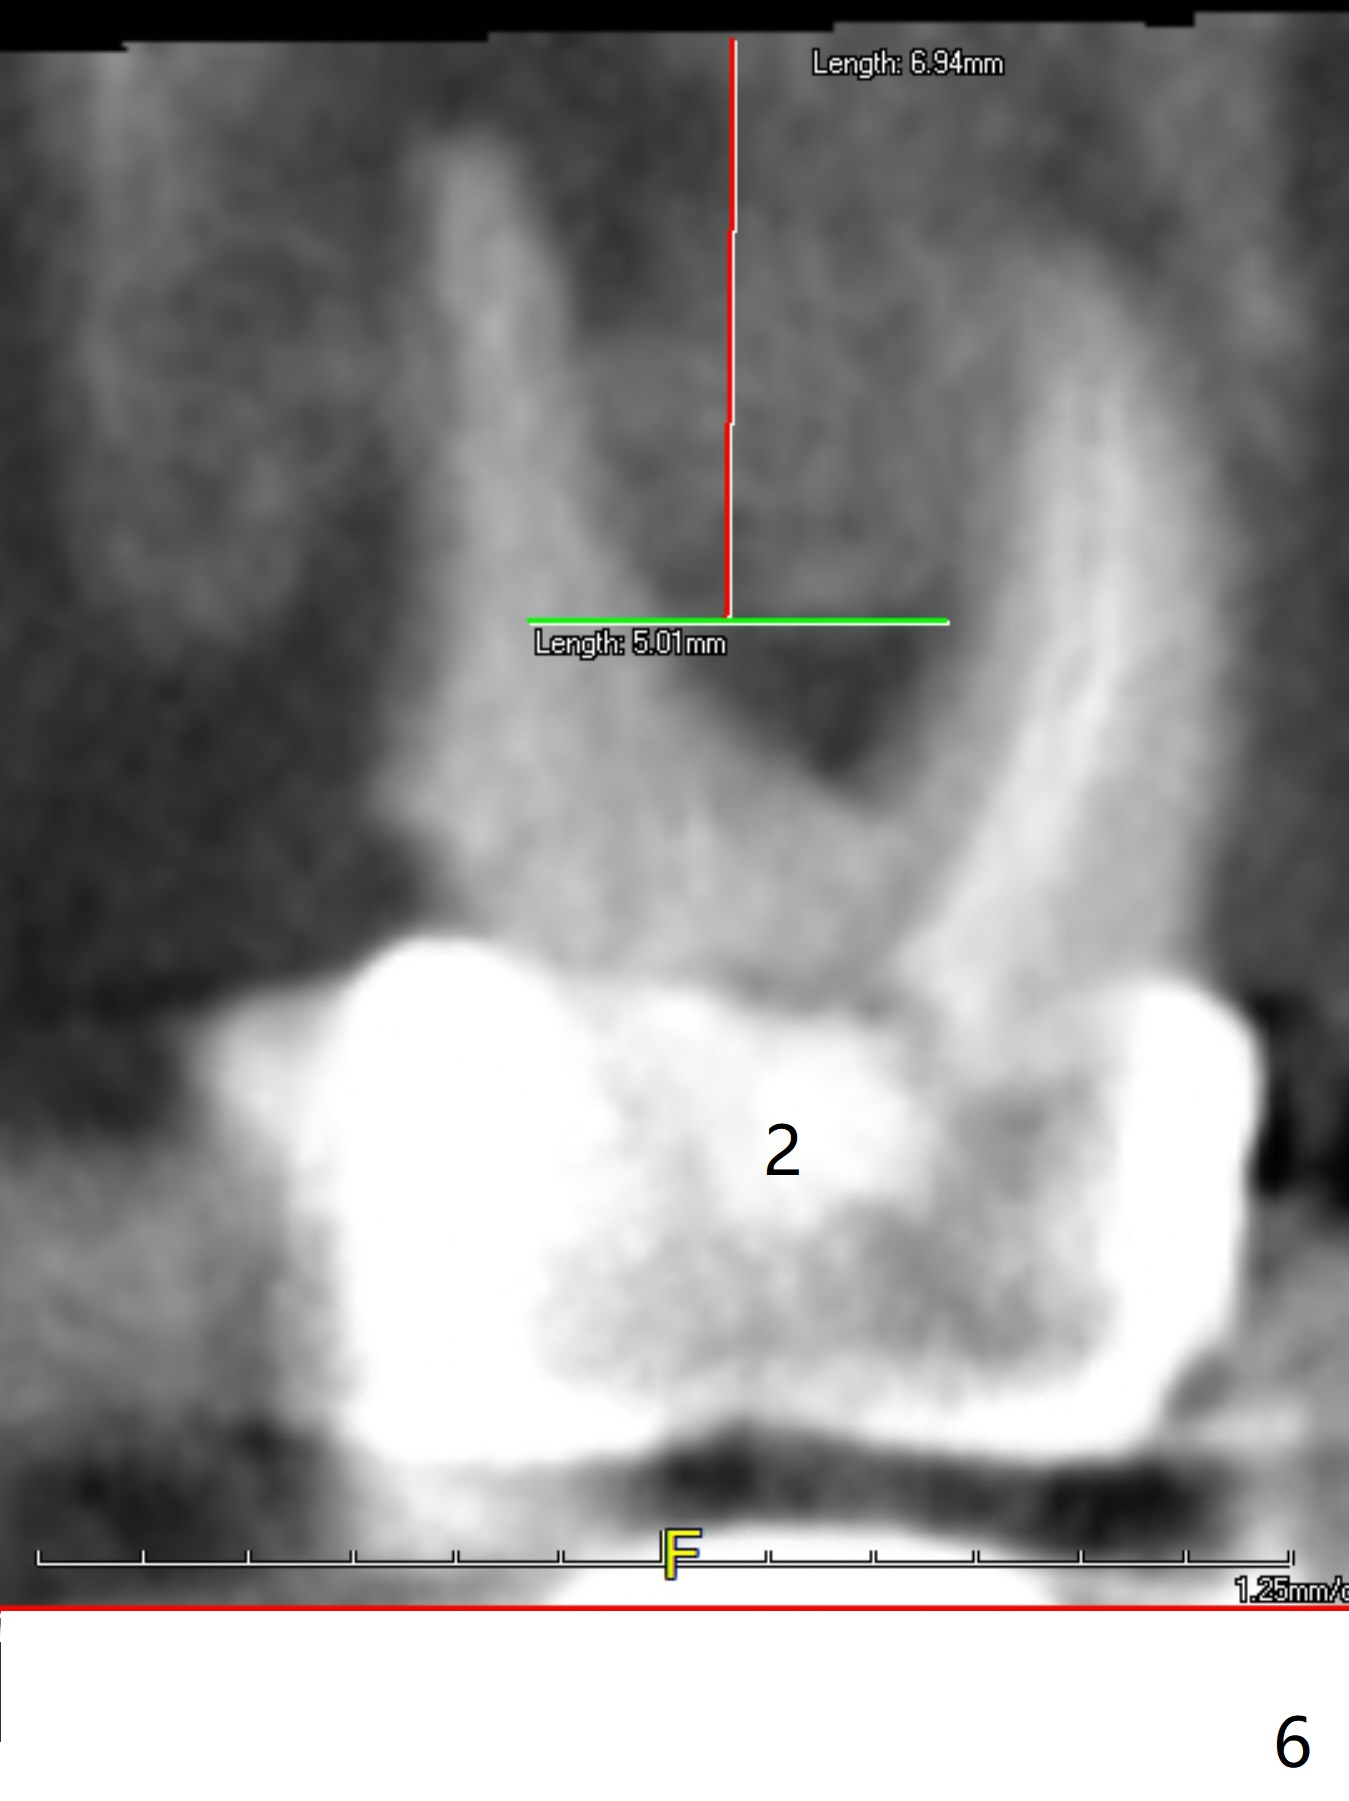

A 43-year-old woman has a failing upper right bridge (Fig.1: #2-5). While the abutment at #5 has apparently palatal open margin (Fig.2,3) and that at #4 has severe palatal bone loss (Fig.4 arrow), that at #2 has the poorest prognosis (Fig.6,7). Panoramic X-ray or PAs will be taken because of CBCT cone cut when the patient returns for #30 and 31 post-implant follow-up. Alginate impression will be taken for the upper right quadrant for provisional. The bridge will be sectioned between #3 and 5 (Fig.1 red lines) to determine salvageability of the abutments at # 4 and 5. If the latter are ok, the abutment at #2 will be extracted (expected to be loose) and implants will be placed at #2 and 3. If #4 is bad while #5 is ok, the former will be extracted and implants will be placed at #2 and 4 with a bridge. If #5 is bad while #4 is ok, implants will be placed at #2, 3 and 5.